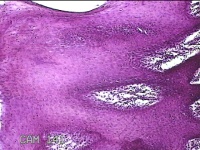

下唇肿物

性别

男

年龄

46岁

临床诊断

口腔黏膜粘液囊肿

一般病史

下唇肿物20余天。

标本名称

大体所见

灰白暗红色肿物1.2x0.7x0.3cm一个,表面光滑。